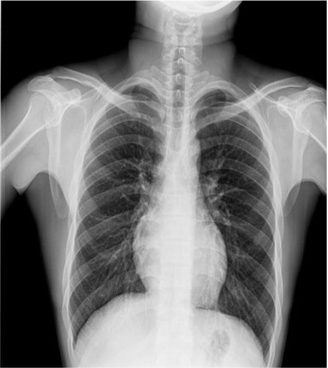

卓越的影像鏈配置是獲得優(yōu)質(zhì)影像的有力保障:普利德車載DR采用高頻高壓發(fā)生器、大熱容量球管確保穩(wěn)定、精確的射線輸出;17X17英寸大尺寸無(wú)線平板探測(cè)器,更大的視野范圍,更高的靜態(tài)空間分辨率,確保呈現(xiàn)清晰影像。

普利德車載DR可進(jìn)行胸部等部位的X射線數(shù)字?jǐn)z影檢查,滿足大規(guī)模體檢及傳染疾病控制需求,尤其在重大疫情預(yù)防等應(yīng)急檢查工作中具有突出優(yōu)勢(shì),為各級(jí)醫(yī)療機(jī)構(gòu)快速應(yīng)對(duì)突發(fā)性公共衛(wèi)生事件提供強(qiáng)大助力,實(shí)力護(hù)航健康之路。